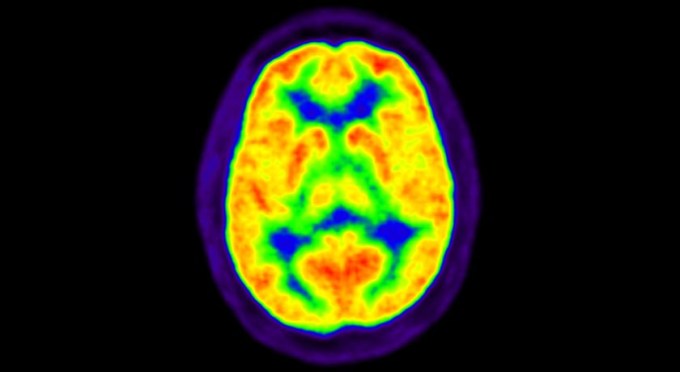

7. Neuroscience

Brain’s protective barrier gets leakier with age

Aging influences the breakdown of the blood-brain barrier, which may contribute to learning and memory problems later in life.